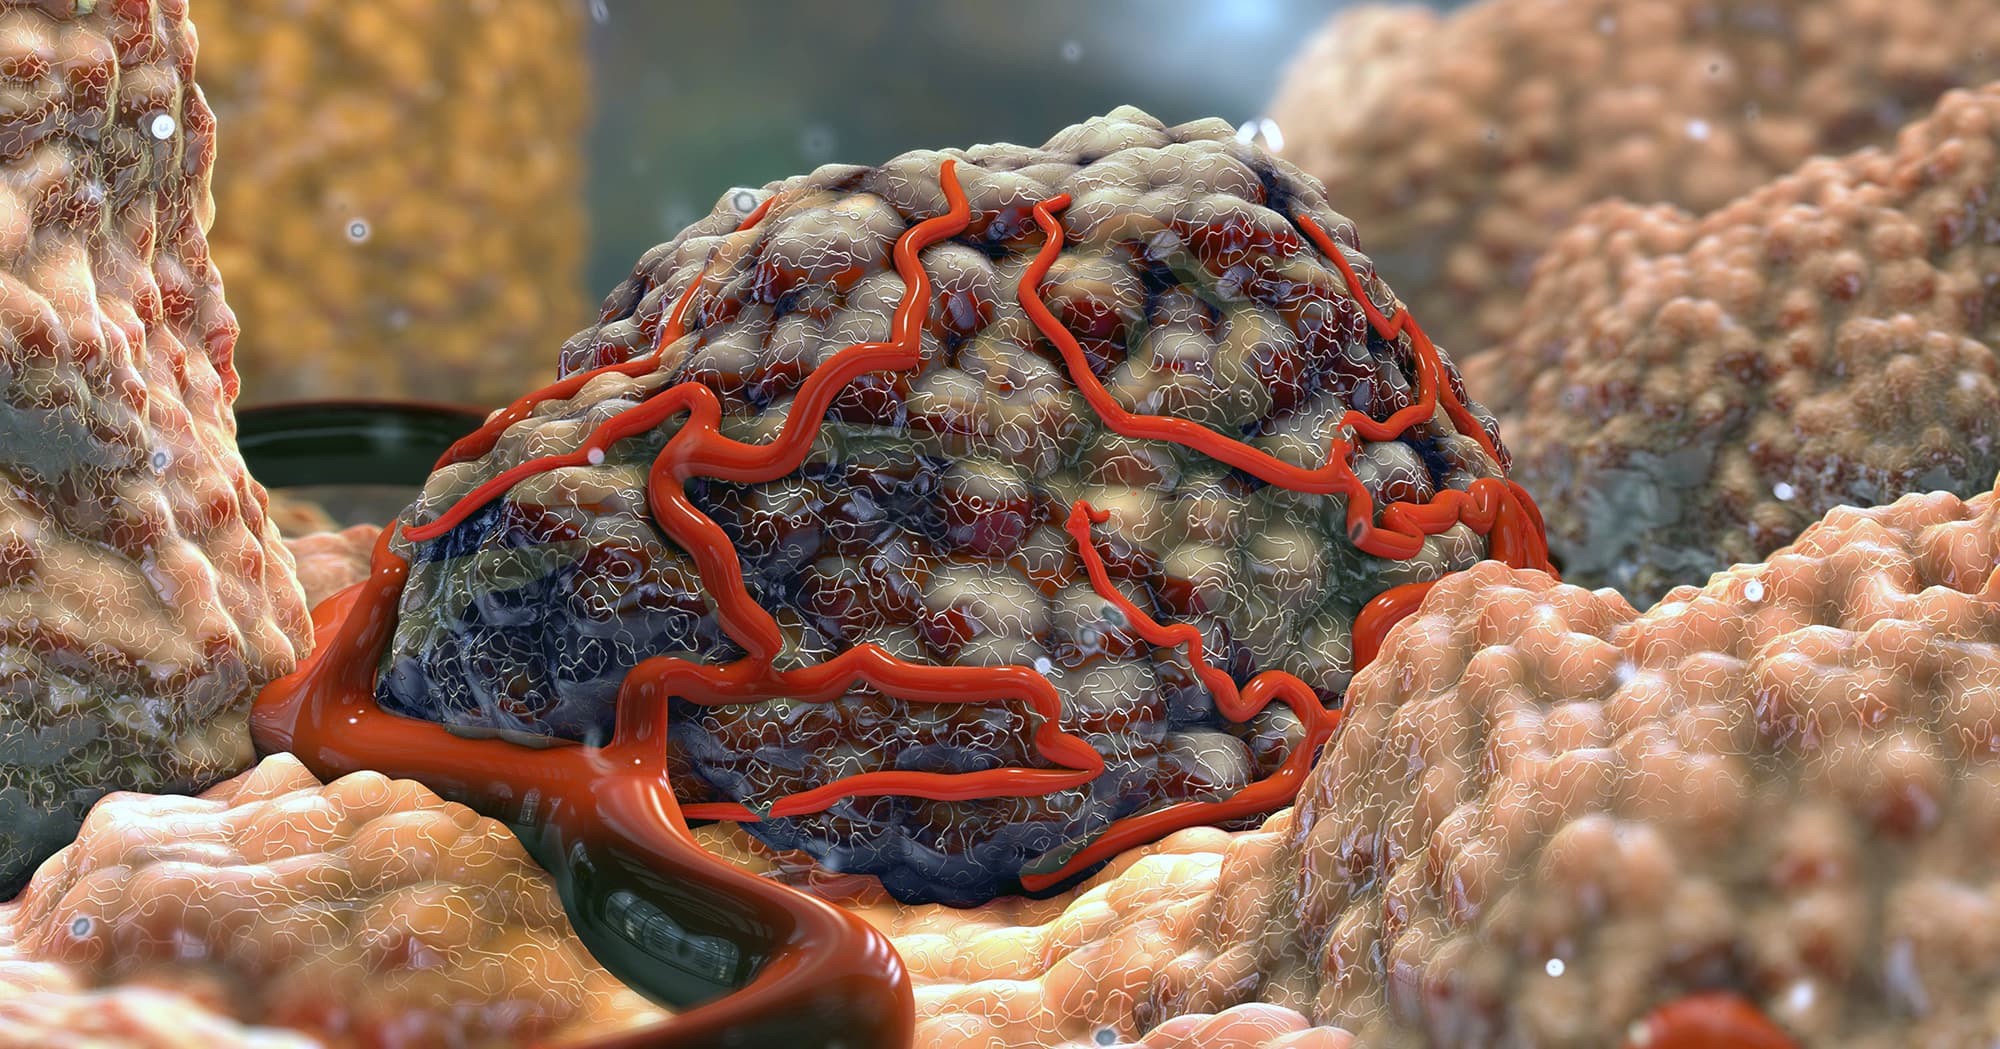

Фото раковой шишки на теле

Раковые шишки могут возникать не только на лице, но и на других частях тела. На фотографиях вы можете увидеть примеры раковых шишек на шее, руках, ногах и туловище. Обратите внимание на различные формы и размеры раковых шишек, а также на их внешний вид.